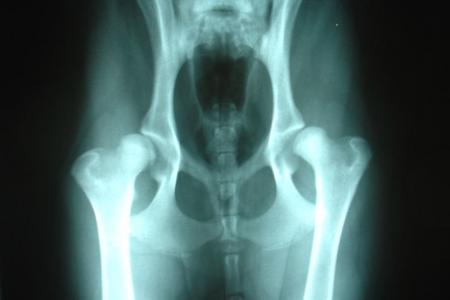

Οι αρθρώσεις επιτελούν ένα σημαντικό και σύνθετο ρόλο στον οργανισμό τον δικό μας όπως και των τετράποδων φίλων μας. Πρέπει να παρέχουν στήριξη, συνδέοντας τα οστά, ταυτόχρονα όμως σταθερότητα και κινητικότητα. Υπολογίζεται ότι τουλάχιστον το 30% των σκύλων θα εμφανίσουν παθήσεις που σχετίζονται με τις αρθρώσεις σε κάποια φάση της ζωής τους. Υπάρχουν παθήσεις οι οποίες εμφανίζονται κυρίως σε νεαρά σκυλιά και υπάρχουν παθήσεις που σχετίζονται με την σταδιακή εκφύλιση των αρθρώσεων οι οποίες εμφανίζονται με την πάροδο του χρόνου σε προχωρημένη ηλικία. Μία άρθρωση για να εμφανίσει κάποιο πρόβλημα θα πρέπει είτε (παρότι αρχικά υγιής) να υφίσταται κάποια υπερβολική φόρτιση είτε να μην έχει την σωστή κατασκευή οπότε ακόμα και με την σωστή φόρτιση να εμφανίσει κάποιο πρόβλημα. Οι παθήσεις των αρθρώσεων διαφέρουν ανάλογα με την φυλή: οι μεγαλόσωμες φυλές εμφανίζουν παθήσεις οι οποίες σχετίζονται κυρίως με την μη σωστή διαμόρφωση, δηλαδή τη μη σωστή κατασκευή κάποιων αρθρώσεων οι οποίες υφίστανται μεγάλες καταπονήσεις και οι κυριότερες από αυτές είναι τα ισχία, ο αγκώνας, ο ώμος και τα γόνατα. Είναι χαρακτηριστικές, πολύ γνωστές σε αυτούς που ασχολούνται με την καθαροαιμία και τις μεγαλόσωμες φυλές, οι παθήσεις όπως η δυσπλασία του ισχίου και η δυσπλασία του αγκώνα. Σήμερα, οποιοσδήποτε καθαρόαιμος σκύλος για να μπορέσει να δώσει απογόνους θα πρέπει να έχει ελεγχθεί για την δυσπλασία του ισχίου και σύντομα απ’ όσο γνωρίζουμε οι κυνολογικοί όμιλοι θα ξεκινήσουν προγράμματα τα οποία θα σχετίζονται και με τον έλεγχο για την σωστή διαμόρφωση του αγκώνα σε ότι αφορά τα σκυλιά που πρόκειται να αναπαραχθούν.

Αυτός θα ξεκινήσει με μια προσεκτική παρατήρηση του τρόπου που βαδίζει, του τρόπου που κάθεται, του τρόπου που σηκώνεται, που ανεβαίνει σκάλες το ζώο μας. Στη συνέχεια, θα ψηλαφήσει τις αρθρώσεις του και θα εντοπίσει πιθανό τριγμό, πιθανό πόνο ή πιθανές αστάθειες που μπορεί να υπάρξουν σε κάποια άρθρωση και στη συνέχεια ανάλογα με την κρίση του, μπορεί να προβεί σε ακτινολογικό έλεγχο των αρθρώσεων προκειμένου να εντοπίσει κάποιες αλλοιώσεις που είναι τόσο μικρές που να μην μπορούν να ψηλαφηθούν ή να φαίνονται με γυμνό μάτι. Οι αρθρώσεις οι οποίες εμφανίζουν προβλήματα με το πέρασμα του χρόνου εμφανίζουν εκφυλιστικές αλλοιώσεις οι οποίες σχετίζονται με πάχυνση του αρθρικού θυλάκου ή με αλλαγή της ποσότητας ή και της ποιότητας του αρθρικού υγρού, που είναι το υγρό το οποίο σαν λιπαντικό λειτουργεί μέσα στην άρθρωση και μειώνει τις τριβές. Ακόμα, μπορούν να σχετίζονται και με αλλοιώσεις του υποκείμενου οστού, δηλαδή του οστού που βρίσκεται κάτω από τον χόνδρο που καλύπτει, προστατεύει και δίνει την ευχέρεια κίνησης της άρθρωσης, το οποίο έχει σαν αποτέλεσμα την δημιουργία οστεοαρθρίτιδας και τη δημιουργία οστεόφυτων. Αυτές είναι μικρές ανώμαλες προεκβολές οστικού ιστού οι οποίες στην αρχή απλά εμποδίζουν την κίνηση και στο μέλλον μπορεί να οδηγήσουν σε πόνο και σε υποβάθμιση της ποιότητας ζωής του ζώου μας.

Σε ότι αφορά τους σκύλους νεαρής ηλικίας και ειδικά καθαρόαιμους σκύλους που εμφανίζουν συγκεκριμένη προδιάθεση για παθήσεις των αρθρώσεων, όπως για παράδειγμα είναι οι γερμανικοί ποιμενικοί με το κλασικό πρόβλημα της δυσπλασίας του ισχίου, άλλες ράτσες όπως τα Λαμπραντόρ με προβλήματα στο ισχίο, με προβλήματα στα γόνατα, με προβλήματα με δυσπλασίες του αγκώνα, όπως είναι κάποια σκυλιά μεσαίων ή μεγαλόσωμων φυλών με τα προβλήματά τους στους χόνδρους, στις κεφαλές του βραχιονίου, όπως είναι οι μικρόσωμες φυλές με τα θέματα εξαρθρήματος επιγονατίδας ή ασηπτικής νέκρωσης της κεφαλής του μηριαίου, θα πρέπει έγκαιρα σε νεαρή ηλικία, από ηλικία λίγων μηνών, να απευθυνόμαστε στον κτηνίατρό μας, να ζητάμε την συνδρομή του, να εξετάζουμε το ζώο μας, προκειμένου να διαπιστώνουμε έγκαιρα αν υπάρχουν τέτοια προβλήματα. Συνιστάται βέβαια, σκύλοι που εμφανίζουν τέτοια προβλήματα, να αποκλείονται από την αναπαραγωγή και να μπαίνουν σε ένα πρόγραμμα μειωμένης καταπόνησης των αρθρώσεών τους, σωστής διατροφής και παροχής συστατικών συμπληρωμάτων διατροφής τα οποία λειτουργούν προστατευτικά για τις αρθρώσεις και μειώνουν την φθορά τους στο πέρασμα του χρόνου, άρα βελτιώνουν και μακροπρόθεσμα την ποιότητα ζωής του κατοικίδιου μας.